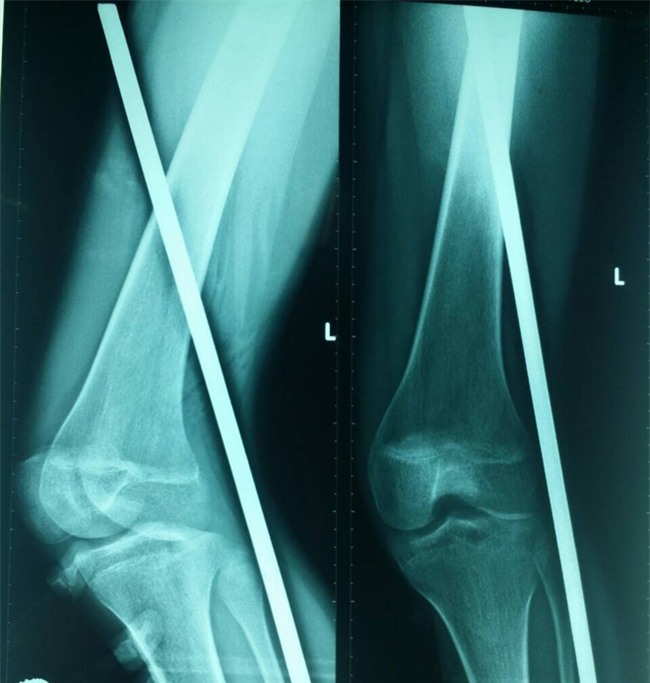

Phim chụp X-quang đoạn sắt đâm xuyên thấu chân bệnh nhân. Ảnh: Bác sĩ cung cấp. |

Kết quả chụp X-quang cho thấy đoạn sắt đâm xuyên phần mềm không làm tổn thương dây thần kinh, mạch máu.